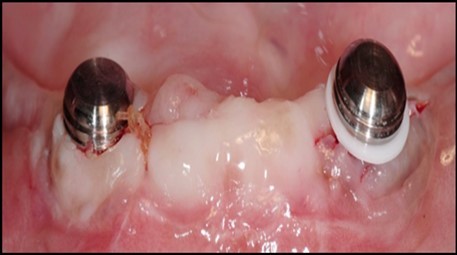

Post operatively after 3 months, osseointegration was evaluated clinically and radiographically (Figure 5a,b) and the implants were well prepared to receive the prosthesis. The second stage surgery was performed in which cover screws were removed and healing abutment were inserted into the implants (Figure 6). After a time period of two weeks, peri-implant soft tissue healing was examined, and existing denture was relined after relieving at the abutment site. Later, the healing abutment is removed using a 1.25 mm hex driver. Internal portion of the implant is irrigated and dried to make sure if it is free of debris and soft tissue. A periodontal probe was used to measure the gingival cuff height at the right and left canine site of implant location. Selected ball abutment were placed onto each implant using 1.25 mm hex driver and 30 Ncm torque wrench (Figure 7A).

Figure 7.(A) View of 2.0mm and 5.0mm post Locator Abutments with a 2.0mm post. (B) Placement of the Locator Abutment after the well of implant has been cleaned with alcohol on a cotton-tipped applicator.